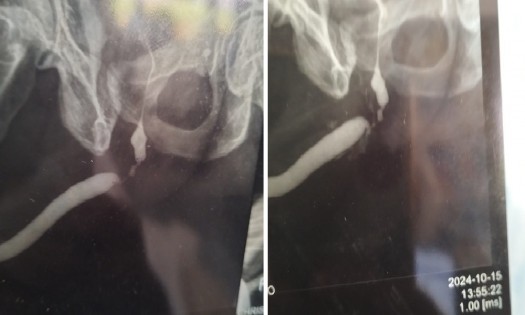

URETHRAL STRICTURE is a narrowing of the urethra—the tube that carries urine out of the body—caused by scar tissue from injury, infections, or medical procedures. This narrowing can lead to a weak or interrupted urine stream, difficulty starting urination, frequent infections, and discomfort.

• Diagnosis: Through a physical exam, imaging tests, or endoscopy.

• Treatment: May include dilation (widening the urethra) or surgical repair (urethroplasty) in severe cases.